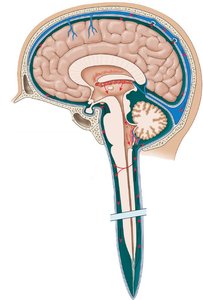

The ventricular system consists of interconnected cavities within the brain that produce and circulate cerebrospinal fluid (CSF). The main ventricles are:

Lateral ventricles: One in each cerebral hemisphere.

Third ventricle: Located in the diencephalon.

Fourth ventricle: Located between the pons and cerebellum, extending into the medulla oblongata.

Passageways include the interventricular foramina (connecting lateral ventricles to the third ventricle) and the cerebral aqueduct (connecting the third and fourth ventricles). The fourth ventricle narrows to become the central canal of the spinal cord.

The dura mater is the outermost meningeal layer, divided into two sublayers:

Periosteal cranial dura: Fused to the periosteum of cranial bones.

Meningeal cranial dura: Inner layer, can form dural folds and contains venous sinuses for blood drainage.

The subdural space lies beneath the dura mater and is normally empty except in cases of disease or trauma.

Arachnoid Mater

The arachnoid mater is the middle meningeal layer, resembling a spider web. The subarachnoid space beneath it contains a delicate network of collagen and elastic fibers (arachnoid trabeculae) and is filled with CSF.

Pia Mater

The pia mater is the innermost layer, anchored to the brain's surface by astrocytes and surrounding cerebral blood vessels that penetrate the brain.

CSF is produced by the choroid plexus in the ventricles, consisting of specialized ependymal cells and permeable capillaries. It is produced in the third and fourth ventricles and extends into the lateral ventricles. CSF flows through the ventricular system, enters the subarachnoid space via openings in the fourth ventricle, circulates around the brain and spinal cord, and is reabsorbed through arachnoid granulations in the superior sagittal sinus.